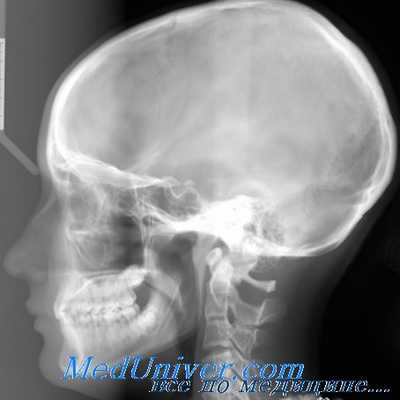

С целью дифференциальной диагностики внутричерепных осложнений, связанных с патологией уха и других ЛОР-органов, используются обзорные рентгенограммы черепа в прямой, боковой и аксиальной проекциях.

Боковые проекции. Поскольку на прямых снимках не выявляются некоторые области (например, передняя, средняя и задняя черепные ямки наслаиваются друг на друга, не видно турецкое седло, не прослеживаются полностью швы покровных костей и т.д.), необходим обзорный рентгеновский снимок в боковой проекции. На нем более четко отображаются анатомические детали черепа, расположенные ближе к кассете, на них накладываются несколько размытые и увеличенные эти же детали удаленной от кассеты стороны. Поэтому для более точной оценки состояния обеих половин черепа целесообразно производить два рентгеновских боковых обзорных снимка и сравнивать их.

При боковой (битемпоральной) обзорной проекции больной лежит на животе или сидит, прижавшись щекой и ухом к кассете. Сагиттальная плоскость головы пациента должна быть строго параллельна плоскости кассеты, голова при этом удерживается фиксатором. Оба глаза находятся на горизонтальном уровне. Центральный луч идет перпендикулярно кассете через середину линии, соединяющей наружный слуховой проход и внутренний угол глазницы.